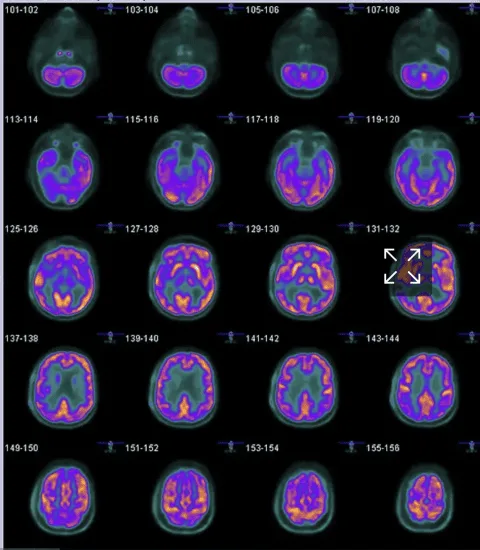

4. Precision in Mapping Brain Activity

- PET is excellent for mapping brain activity, helping to diagnose conditions like Alzheimer’s, Parkinson’s, and epilepsy. MRI offers better structural details, but PET reveals functional changes, which is crucial in diagnosing neurological disorders.